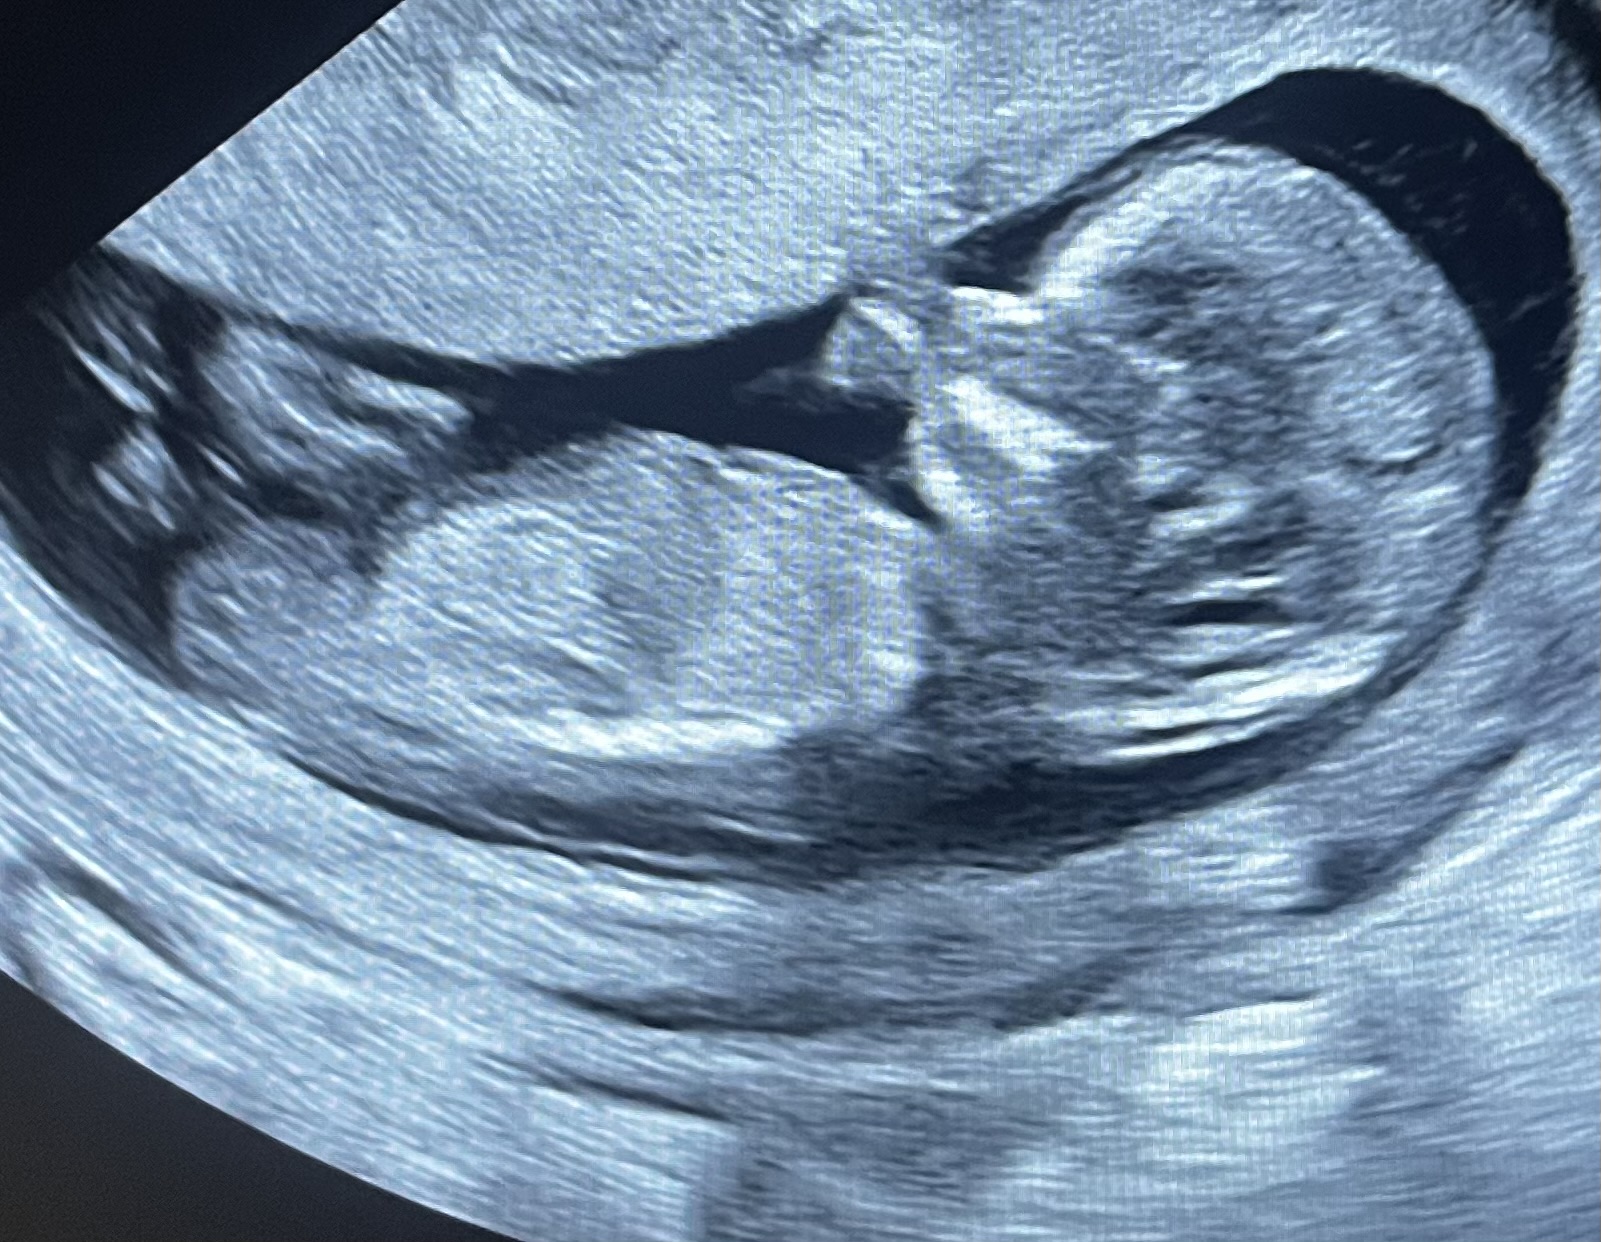

I Скрининг 12 недель #1 в ЖК

Девочка) череп красивый, круглый, женский

Похоже на девочку 🩷